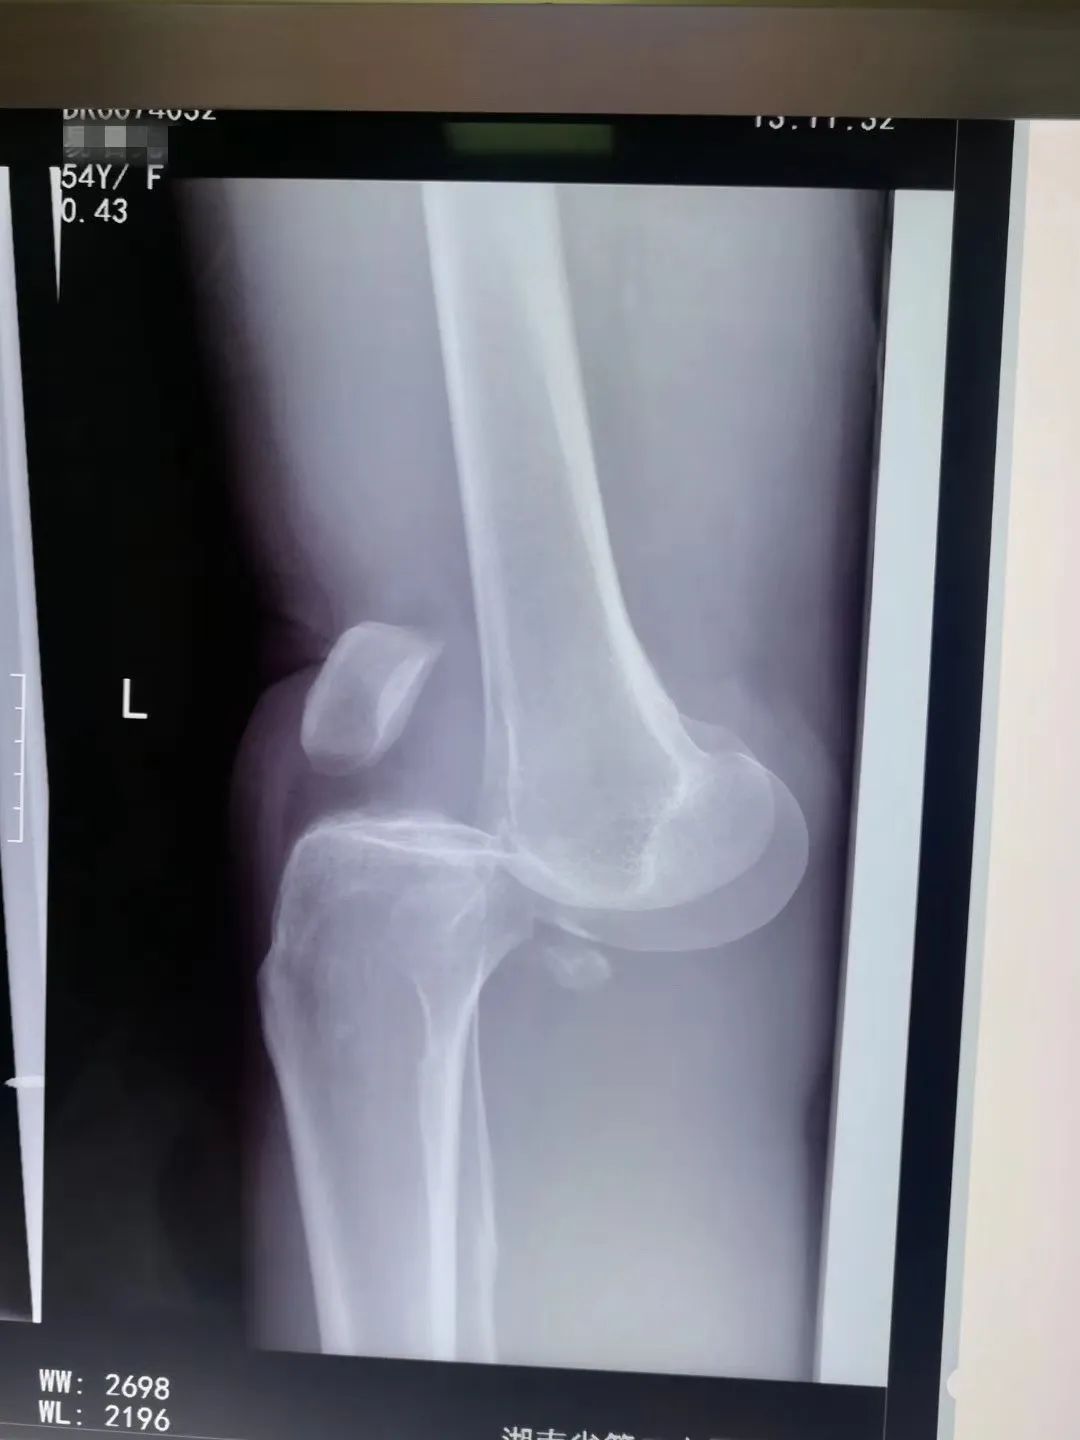

家住岳麓区的小李(化名),就饱受“关节积液”的折磨。去年,10月份,小李不慎从高处摔下导致股骨往后脱位,手术一个月后,小李的左腿膝关节表面肿胀依然非常明显,疼痛难忍,连走路、上下楼都困难。

11月18日,小李来到三真康复梅溪湖院区颈肩腰腿痛专科门诊,找欧阳文湘医生寻求治疗。小李做了一个关节超声报告,报告显示:左膝关节腔内,存在积液。

欧阳医生在B超引导下,成功穿出共约70毫升的淡红色液体。当积液抽出的那一刻,小李感觉到左腿膝盖处的肿胀疼痛感立马减轻了!后期结合相应的康复训练,现在的小李已经生龙活虎了!